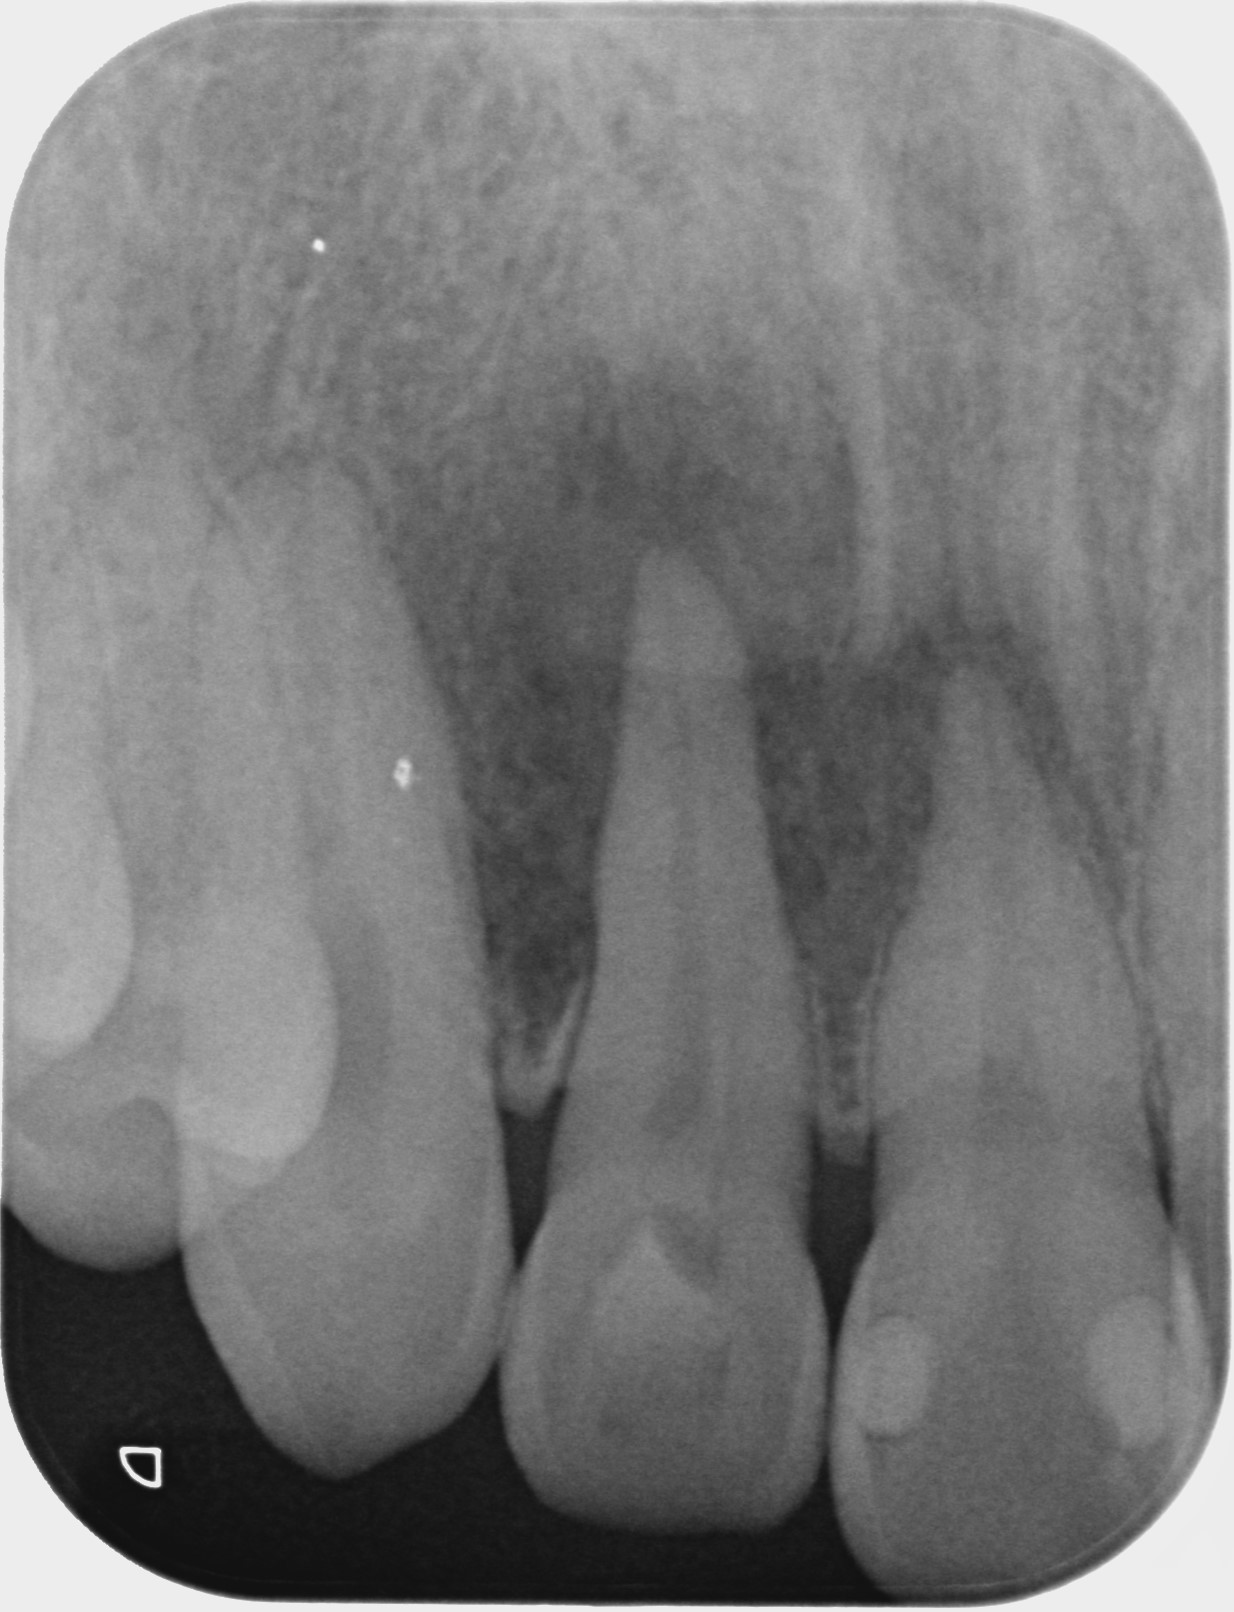

本症例は20代男性、右上前歯が痛い。

右上前歯が痛いとの主訴で来院。歯肉の腫れはないが、何もしなくても痛みあり。デンタルX線写真を撮影したところ右上1番・2番の根尖部を含む大きな根尖病巣と思われる透過像を認める。根管治療を行い根充後しばらくは違和感が続いたため、違和感消失後、補綴処置に至る。術後8年を経過しているが問題なし。